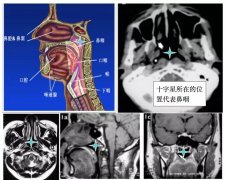

人体的上消化呼吸道自上而下分为鼻咽、口咽、喉咽。鼻咽的位置很隐蔽,位于人体中心线附近,上有颅底骨质和大脑,前有鼻腔,后有脊柱脊髓,两侧有下颌骨和腮腺,下面是硬腭和软腭(图1),从人体外部是看不见、摸不着的,必须由专业医生借助一定的检查设备才能发现。

(图一)